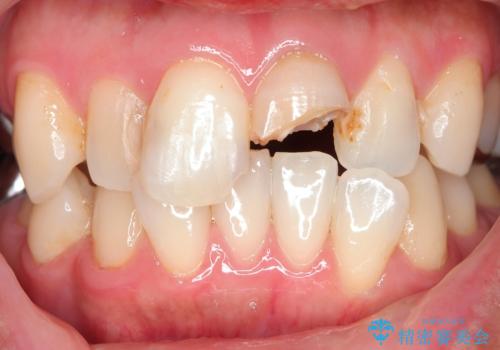

転んで折れた前歯セラミック治療で審美改善

- 自転車で転倒してしまい、前歯を折ってしまい、痛みと見た目の改善を希望され来院されました。

もともと根管治療の為されて歯が折れてしまっているので、根管治療を行い審美的なセラミック治療を行う治療計画としました。